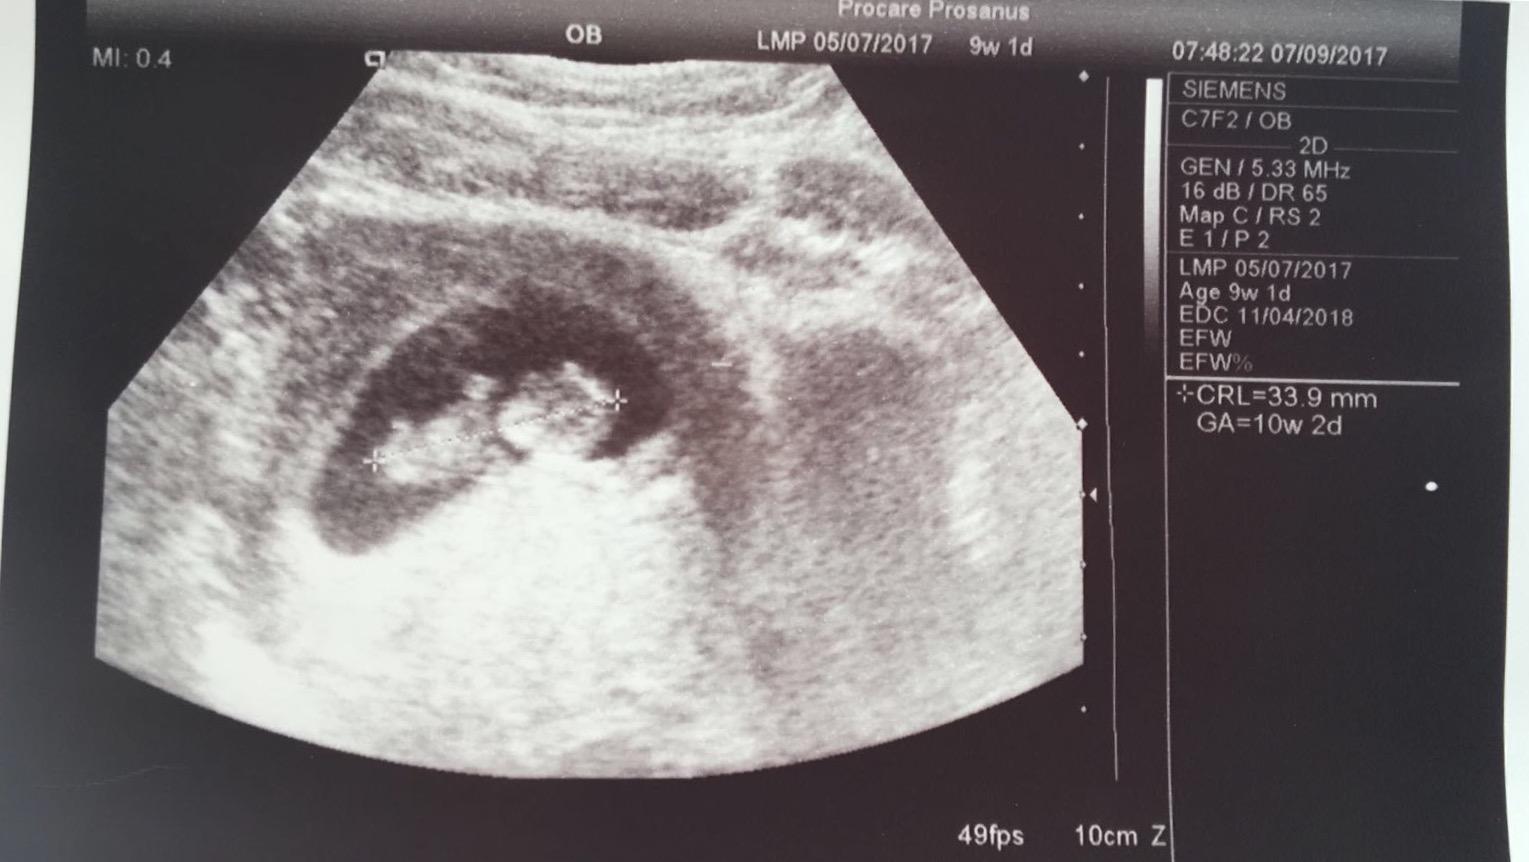

Dievcence az dnes som bola prvykrat u lekarky, po mesiaci tryzniveho cakania, tak mame potvrdene 8+3 dnes 😉